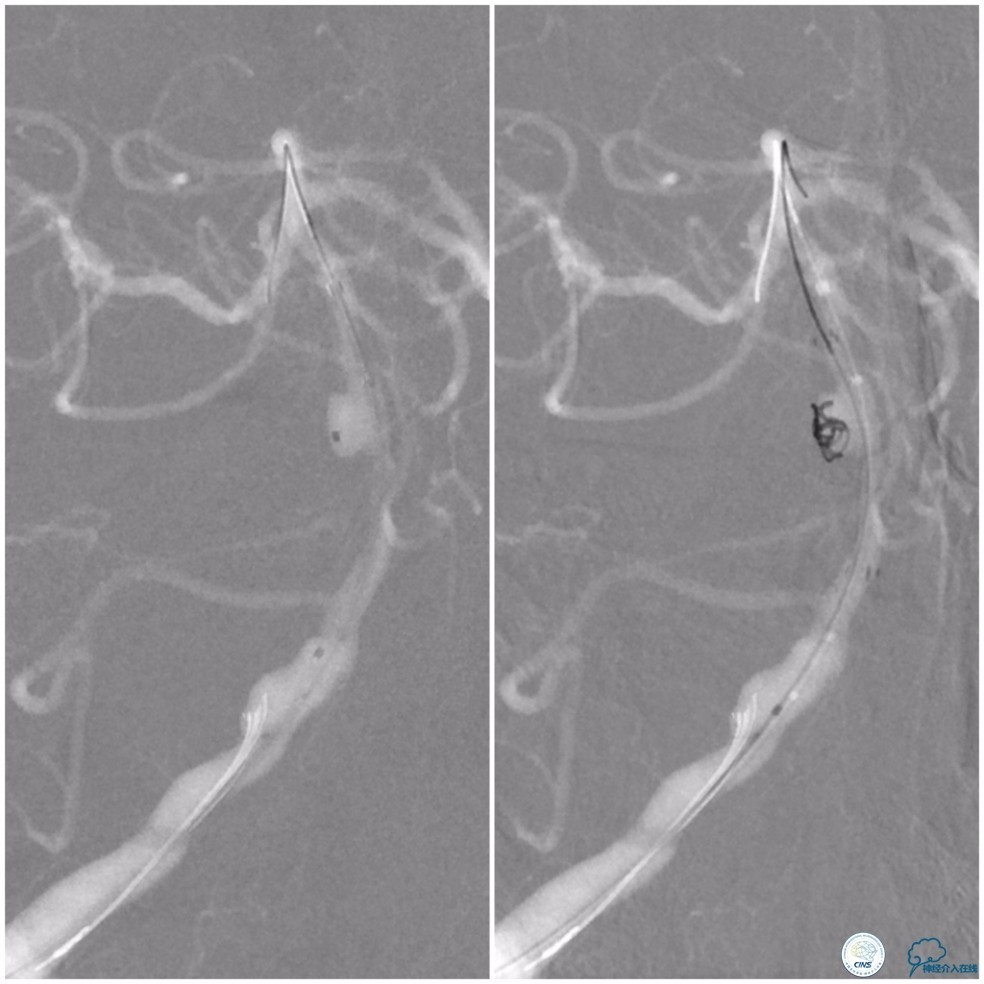

全麻下,右股动脉穿刺,因8F导引导管不能通过右椎动脉V1段,改用6F导引导管置于右椎动脉V2段,穿刺左股动脉放置5F导引导管用于栓塞动脉瘤入路。Transend微导丝(0.014″,300cm)通过基底动脉狭窄段,放置在右大脑后动脉P2段后选择Gateway球囊(2.0mm×15mm)先预扩狭窄(图10)。

图10

Wingspan支架(3.0mm× 20mm)系统到位后,经5F导引导管放置Echelon-10微导管至动脉瘤腔内,释放Wingspan支架,进行动脉瘤栓塞(图11)。

图11